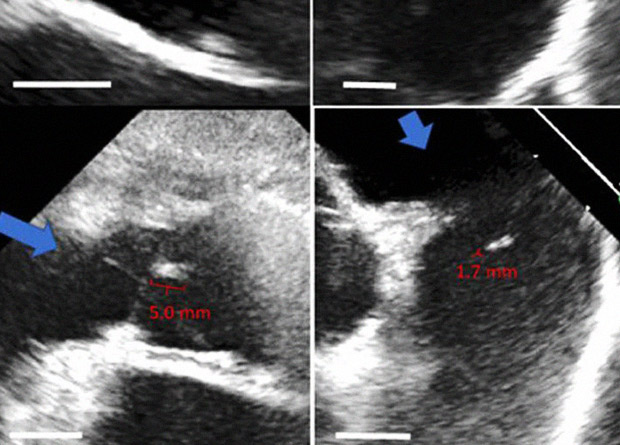

Команда биологов под руководством Роберта Транкилло (Robert Tranquillo) из Миннесотского университета уже не первый год ведет разработку новых сердечных клапанов, которые бы подстраивались под растущий детский организм. Для получения материала для клапанов исследователи предлагают выращивать в лабораторных условиях из фибробластов ткани, которые образовывают внеклеточный матрикс – сеть коллагеновых волокон. Клетки